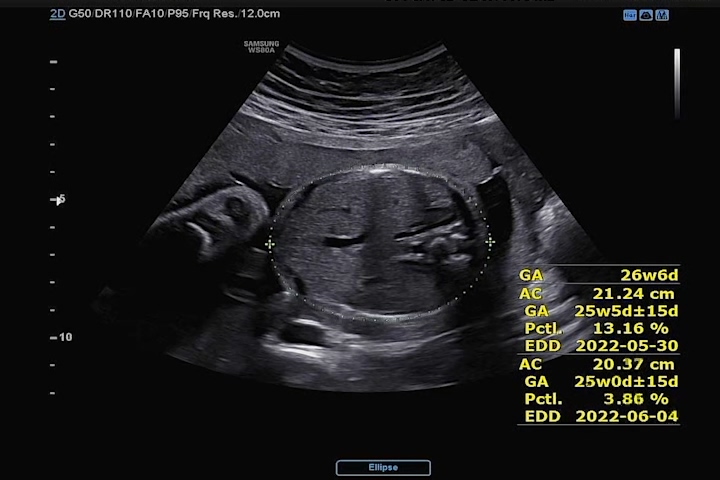

저번 수치에 비해 여전히 우리 까꿍이 머리둘레는 주수에 평균치에 비해 살짝 크고, 배둘레는 약간 왜소했으며 다리는 평균치로 돌아왔다. 아내는 배 둘레가 작다고 해서 놀라 했지만 미비한 정도라고 신경 안 써도 된다고 하였다. 하지만 아내는 검사 후 잘 먹고 푹 숴야겠다며 다짐을 했다. ㅎㅎ